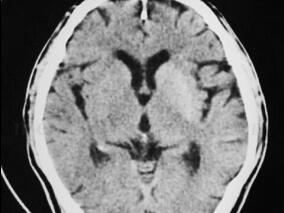

1小时条评论女,66岁,右利手。 主诉:言语不能、四肢活动不灵6天,加重1天。 病史:患者6天前晨起活动中出现头晕、言语困难、四肢活动不灵,可少量进食,无明显呛咳,时而糊涂,强哭,不识家人,伴尿失禁。行头颅CT检查:双侧脑室旁、基底节及脑桥小片低密度影(与2月前头颅C...